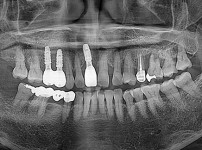

임플란트-전후사진1

임플란트-전후사진2

임플란트-전후사진3

임플란트-전후사진4

임플란트-전후사진5

임플란트-전후사진6

치과를-선택할-때-꼭-확인하세요-서울숙면치과-임플란트-전후사진